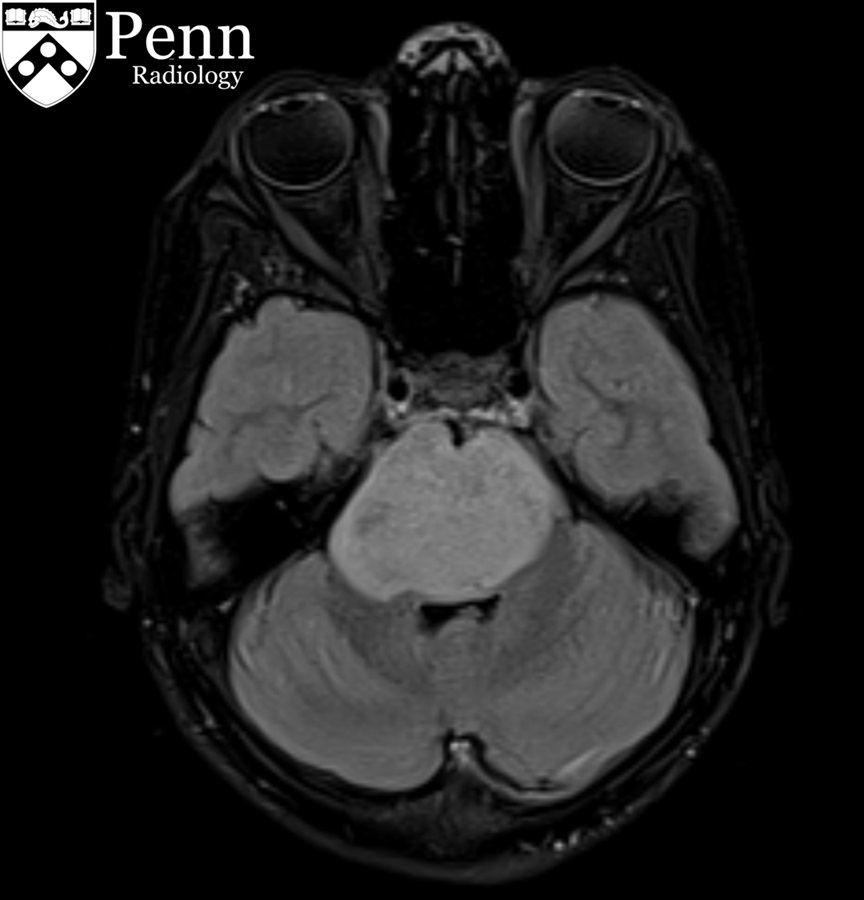

Septo-optic dysplasia (SOD)

Selected image of coronal T2-weighted sequence showed the normal olfactory nerves (within the red cycles).

Selected image of coronal T2-weighted sequence showed point-down appearance of the anterior horns of the bilateral lateral ventricles (red arrows).

Selected image of sagittal T1-weighted sequence showed the ectopic posterior pituitary gland at the roof of the third ventricle (red circle).

Case Discussion

This is a case where most of the septo-optic dysplasia features are nicely demonstrated.

Hypoplastic optic nerves and chiasm, absence septum pellucidum with resultant typical configuration of the anterior horns of the lateral ventricles, along with ectopia of the posterior pituitary gland. On the other hand, the globes are intact and the olfactory bulbs are present with no evidence of associated parenchymal abnormality.